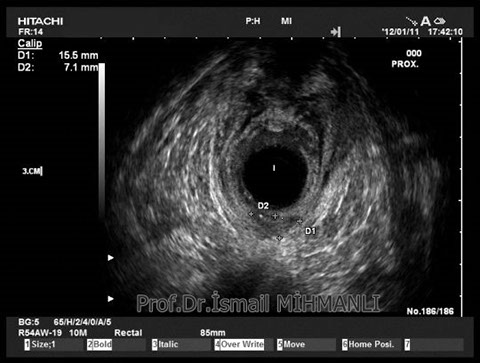

PERİANAL FİSTÜLLER Perianal fistül ve abselerin intersfinkterik anal bez iltihabından kaynaklandığı düşünülmektedir. Crohn hastalarında perianal enflamatuvar hastalık sıktır. İntersfinkterik mesafedeki enfeksiyon yukarıda rektuma, aşağıda cilde, yanlarda dış sfinkteri geçerek iskiyoanal mesafeye uzanabilir. Primer fistülün sfinkterler ile ilişkisini ve abse veya sekonder dal varlığını ameliyat öncesi bilmek, tedavi planı açısından önemlidir. İskiyoanal ve iskiyorektal mesafe tutulmamışsa hastalık daha kolay tedavi edilir. Bu mesafelerde abse veya sekonder bir dal varsa fistül komplekstir ve tedavisi kompleks olmayan fistüle göre değişik olabilir. Bundan dolayı, primer fistül traktı anatomik yerleşimine göre geleneksel olarak sınıflandırılır. Bu sınıflama dörde ayrılır: 1- İntersfinkterik (iç ve dış sfinkter arasında), 2- Transsfinkterik (dış sfinkteri geçerek iskiyoanal veya iskiyorektal mesafeye ulaşmış), 3- Suprasfinkterik (intersfinkterik plandan yukarı doğru uzanan traktüs puborektal kasın Genel Gaz ve Dışkı Kaçırma (Anal İnkontinans) Perianal Fistüller Rektal Tümörler Anal Tümörler Kabızlık Yazılarımız üstündeki bir seviyeden yana kıvrılarak tekrar aşağıya iskiyoanal mesafeye uzanmış), 4- Ekstrasfinkterik (sfinkterlerin dış tarafında rektumdan direkt olarak perianal cilde uzanan traktüs). Endoanal ultrason ile hem primer fistül, hem de varsa sekonder dal ve abse doğru bir şekilde tanınır. Endoanal ultrason ile fistülün anal kanala açılan kısmını (iç uç) görmek kolaydır. Bu hastalarda sfinkter defektlerine de rastlanmaktadır. Sfinkter defekti endoanal ultrason ile kolaylıkla tespit edilir. (bkz. anal inkontinans) Perianal fistül şikayeti olan hastaların az kısmında endoanal ultrason ile bir şey görülemez ise endoanal ultrason probuna ek olarak lineer prob ile anal kanal çevresine bakmak yararlıdır. Çünkü anal kanal bileşenlerinin uzağındaki bir enflamasyon ancak bu problar ile tanınabilir.

Crohn hastasında parİanal enflamatuvar hastalık